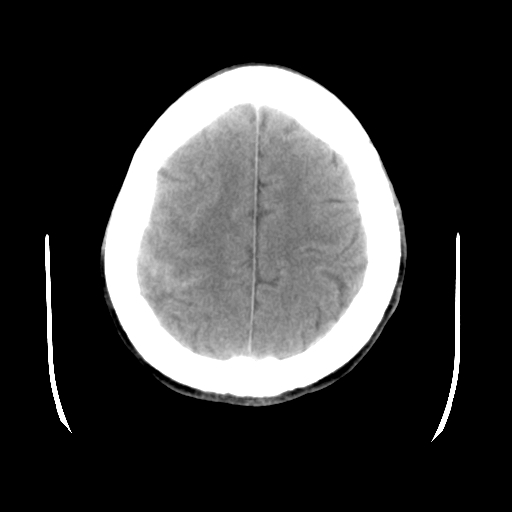

男,51岁,头外伤一小时,呕吐两次。

1)左侧中颅窝蝶骨翼后方硬膜外血肿。2)左侧颞顶部硬膜下血肿。3)蛛网膜下腔出血。4)左侧筛窦及双侧蝶窦炎症(或积血)。5)左侧额部头皮软组织肿胀。